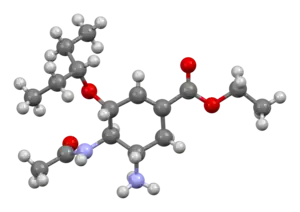

IUPAC name

| Formula | C16H28N2O4 |

| Molar mass | 312.410 g·mol−1 |

| 3D model (JSmol) | |

SMILES

InChI

Mechanism of action

Oseltamivir is a neuraminidase inhibitor, a competitive inhibitor of influenza's neuraminidase enzyme. The enzyme cleaves the sialic acid which is found on glycoproteins on the surface of human cells that helps new virions to exit the cell. Thus oseltamivir prevents new viral particles from being released.[26]